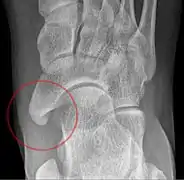

Lateral projection of type 2

Type 2

- Type 2: Triangular or heart-shaped ossicle measuring up to 12 mm, which represents a secondary ossification center connected to the navicular tuberosity by a 1–2 mm layer of fibrocartilage or hyaline cartilage. Portions of the posterior tibialis tendon sometimes insert onto the accessory ossicle, which can cause dysfunction, and therefore, symptoms.